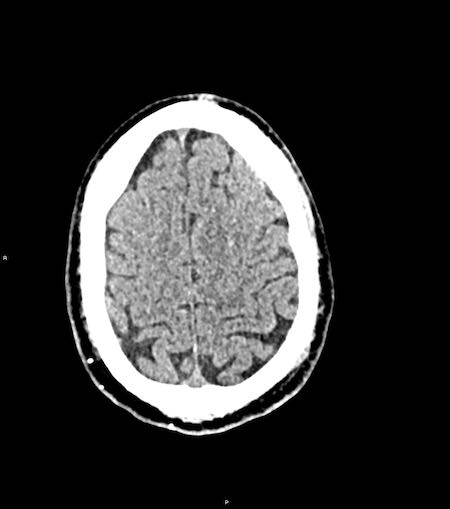

Tụ máu dưới màng cứng đồng tỷ trọng

Khi tụ máu dưới màng cứng tiến triển theo thời gian, tỷ trọng của khối tụ máu sẽ giảm dần và có thể tương đương với tỷ trọng của nhu mô não, khiến việc phát hiện tổn thương trở nên khó khăn.

Đây là trường hợp tụ máu dưới màng cứng đồng tỷ trọng rất khó phát hiện (các mũi tên).

Lưu ý rằng ở mức cắt cao hơn có tụ máu dưới màng cứng hai bên.